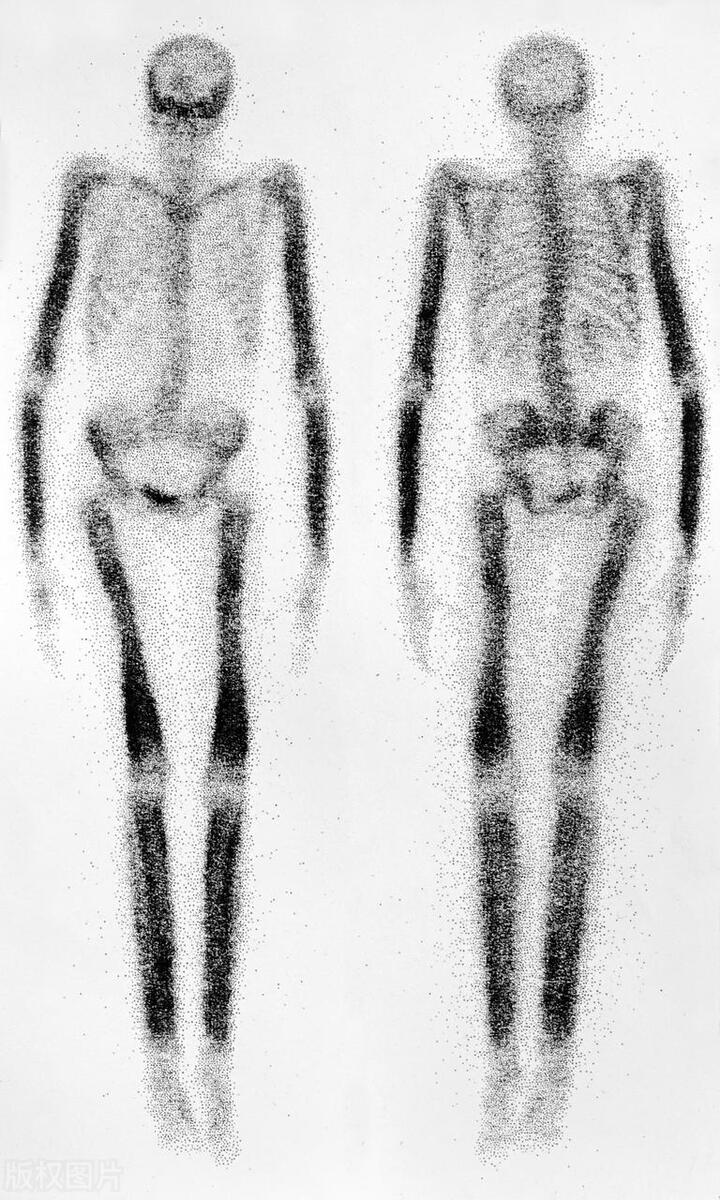

1.骨扫描:骨扫描显示了多个骨骼部位的异常区域,包括脊柱、盆骨、以及肋骨。这些异常区域表现为亮点,提示可能存在骨转移。

1.骨扫描:骨扫描是检测骨转移的常用方法之一。它可以显示骨骼中的异常区域,尤其对于脊柱转移的病灶具有高度敏感性。